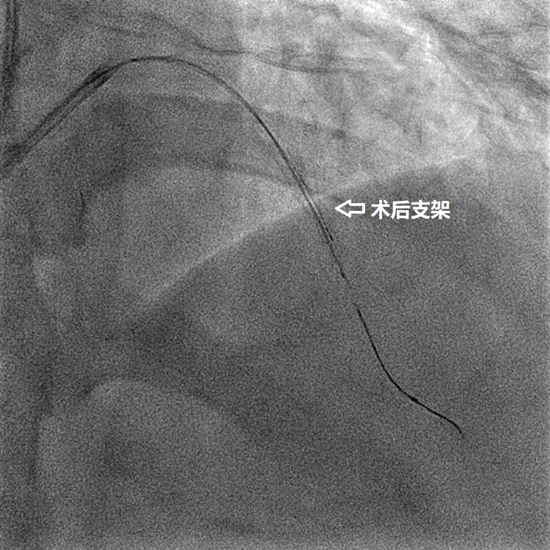

经过充分的术前准备,周密制定的手术方案,以及手术推演,8月26日下午,韩江莉顺利经桡动脉入路为患者进行了IVUS检查。结果显示,左前降支最小管腔面积仅1.86mm2,伴有270°钙化。经使用切割球囊充分预扩张后顺利植入支架。IVUS检查提示,支架膨胀及贴壁良好,无边缘夹层等情况。术中进一步对冠脉CTA报告的右冠状动脉严重病变部位进行IVUS检查,显示血管最小管腔开放面积为6.12mm2,为钙化纤维脂质斑块,提示该病变尚不需介入治疗。

术后血管内超声(IVUS)显示支架膨胀完全,支架边缘没有夹层,手术成功。

术后X线下支架显影